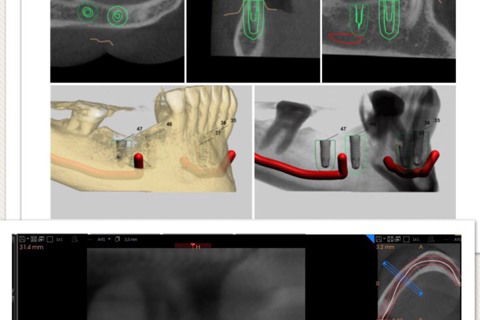

Planejamento virtual e tomografia final

tomografia final comprovando quês técnica é segura e precisa